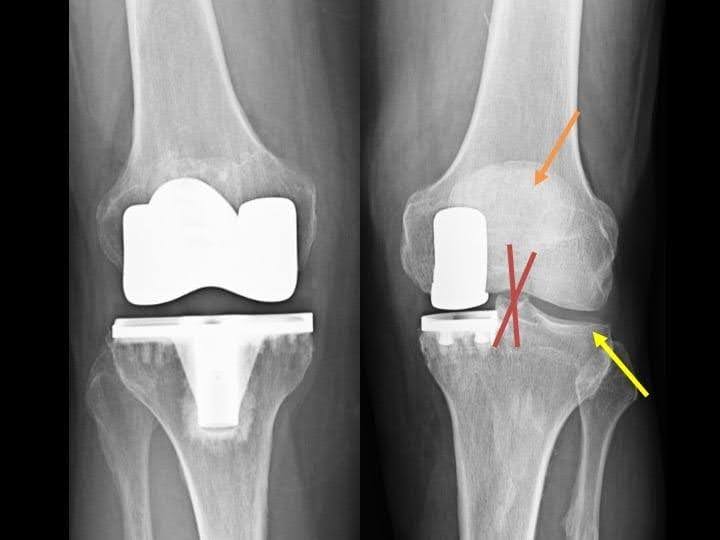

Capitolo 6 – Allineamento nella protesi monocompartimentale mediale

Un corretto allineamento dell’impianto è fondamentale per evitare che si usuri precocemente. Ecco alcuni aspetti importanti da considerare per ottenere un buon allineamento:

- Posizionamento della componente tibiale: un’inclinazione di 2° verso l’interno (varo) aiuta a distribuire bene i carichi.

- Posizionamento della componente femorale: una correzione eccessiva può causare usura nel compartimento laterale del ginocchio.

- Inclinazione posterioredella tibia (slope): tra 3° e 7°, per evitare che il ginocchio tenda a scivolare all’indietro in modo anomalo.

Se l’allineamento non è corretto, si possono avere problemi:

- Correzione eccessiva (>2° in valgo): può portare a sviluppare artrosi nel compartimento laterale.

- Correzione insufficiente (>5° in varo): può causare l’allentamento dell’impianto e un fallimento precoce dell’intervento.

Tre tipi di asse meccanico dopo un’osteotomia tibiale alta (HTO): Se l’asse del ginocchio è in varo (ginocchio “a parentesi”) o neutro, si può valutare una protesi monocompartimentale. Se l’asse è in valgo (ginocchio “a X”), è necessaria una protesi totale.